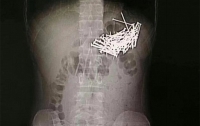

Китаец съел 87 гвоздей после ссоры с девушкой

Житель Индии заедал депрессию монетами и гвоздями

Индийские хирурги достали из мужчины 600 гвоздей